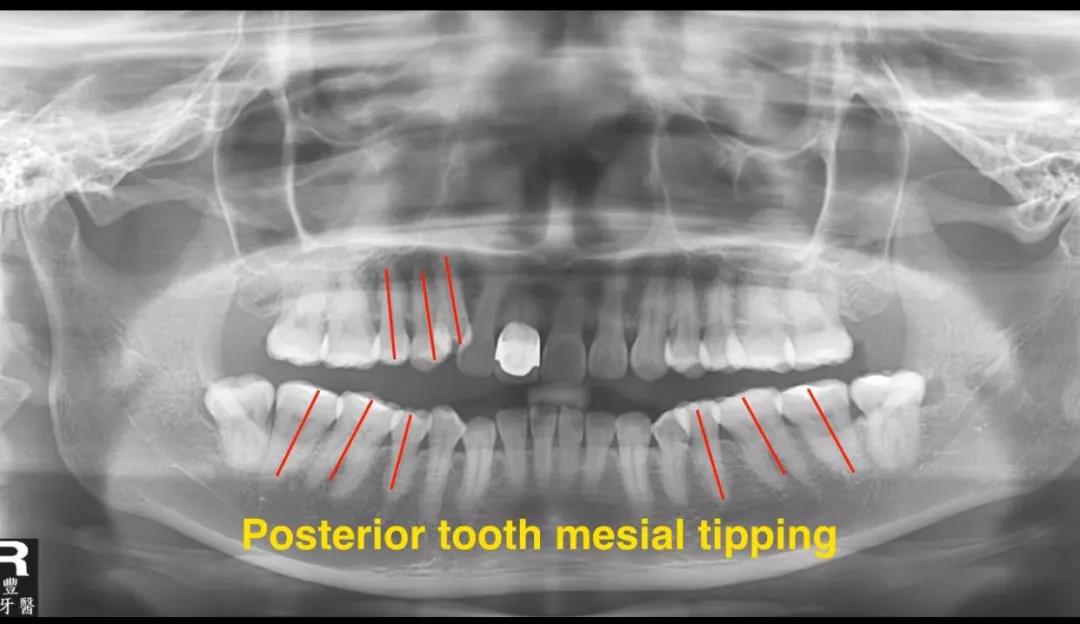

从全景片上分析,上下颌后牙都有近中倾斜的情况,下颌智齿存在。

前后全景片的对比显示,一开始后牙是近中倾斜的,通过治疗,矫治后后牙直立,牙根平行度改善明显。

在全景片上看到本来近中倾斜的后牙扶正了,牙根的平行性得到改善。